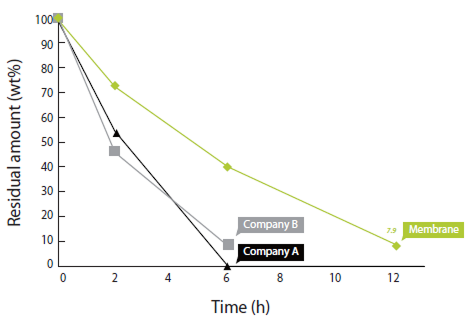

A highly pure type I collagen barrier designed for ease of use, dual-side application, and up to 6 months of membrane function—ideal for GBR, sinus lifts, and ridge preservation.